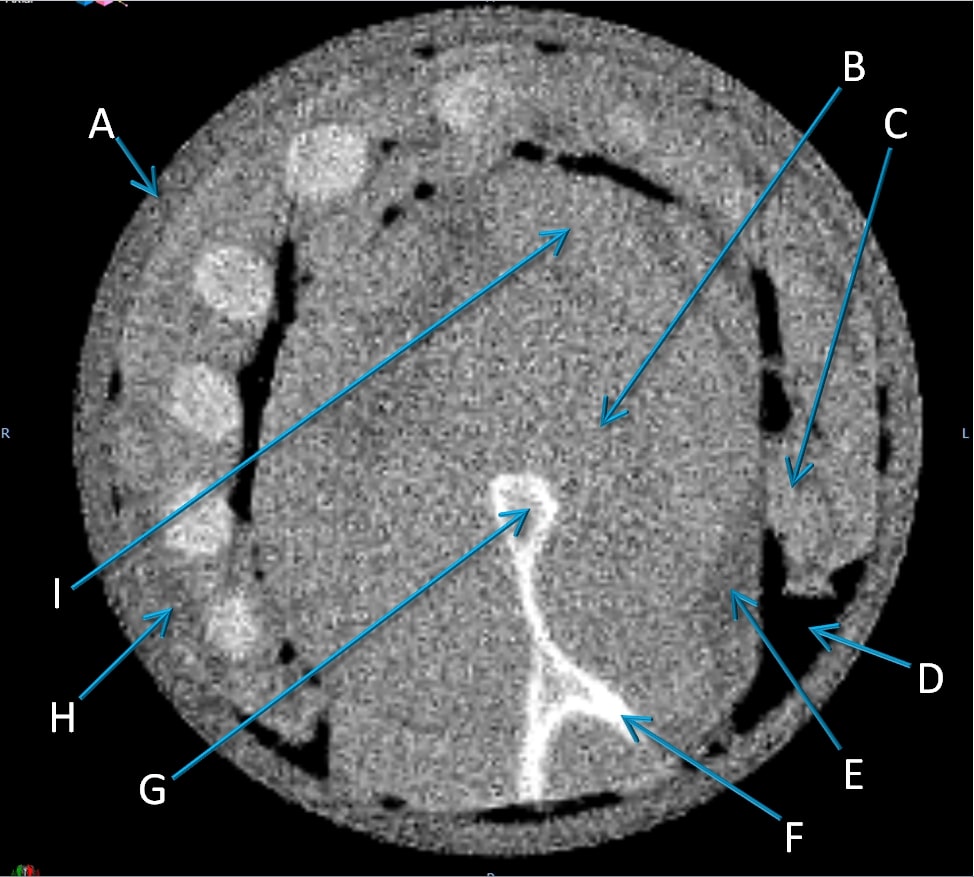

3.C. Comparison of pCT and x-ray CT for porcine pectoral girdle and ribs

We analyzed RSP differences between pCT and x-ray CT for 10 different regions in the porcine pectoral girdle and ribs sample, with examples of regions for one slice indicated in Fig. 5. We found RSP differences of 0.6% or less for all soft tissues, both muscle and adipose, as shown in Table 2. We see a slightly larger difference of 1.9% in the rib trabecular bone, and a much larger difference of 6.9% in the compact bone. The observed 4.1% difference in the blue wax surrounding the sample is not surprising, as the Hounsfield-to-RSP conversion was not calibrated for that type of material.

Due to multiple Coulomb scattering, the pCT image appears less sharp than the x-ray CT image, as shown in the single slice comparison in Fig. 5. The pCT image is still able to distinguish between muscle and fat tissue and compact and trabecular bone.